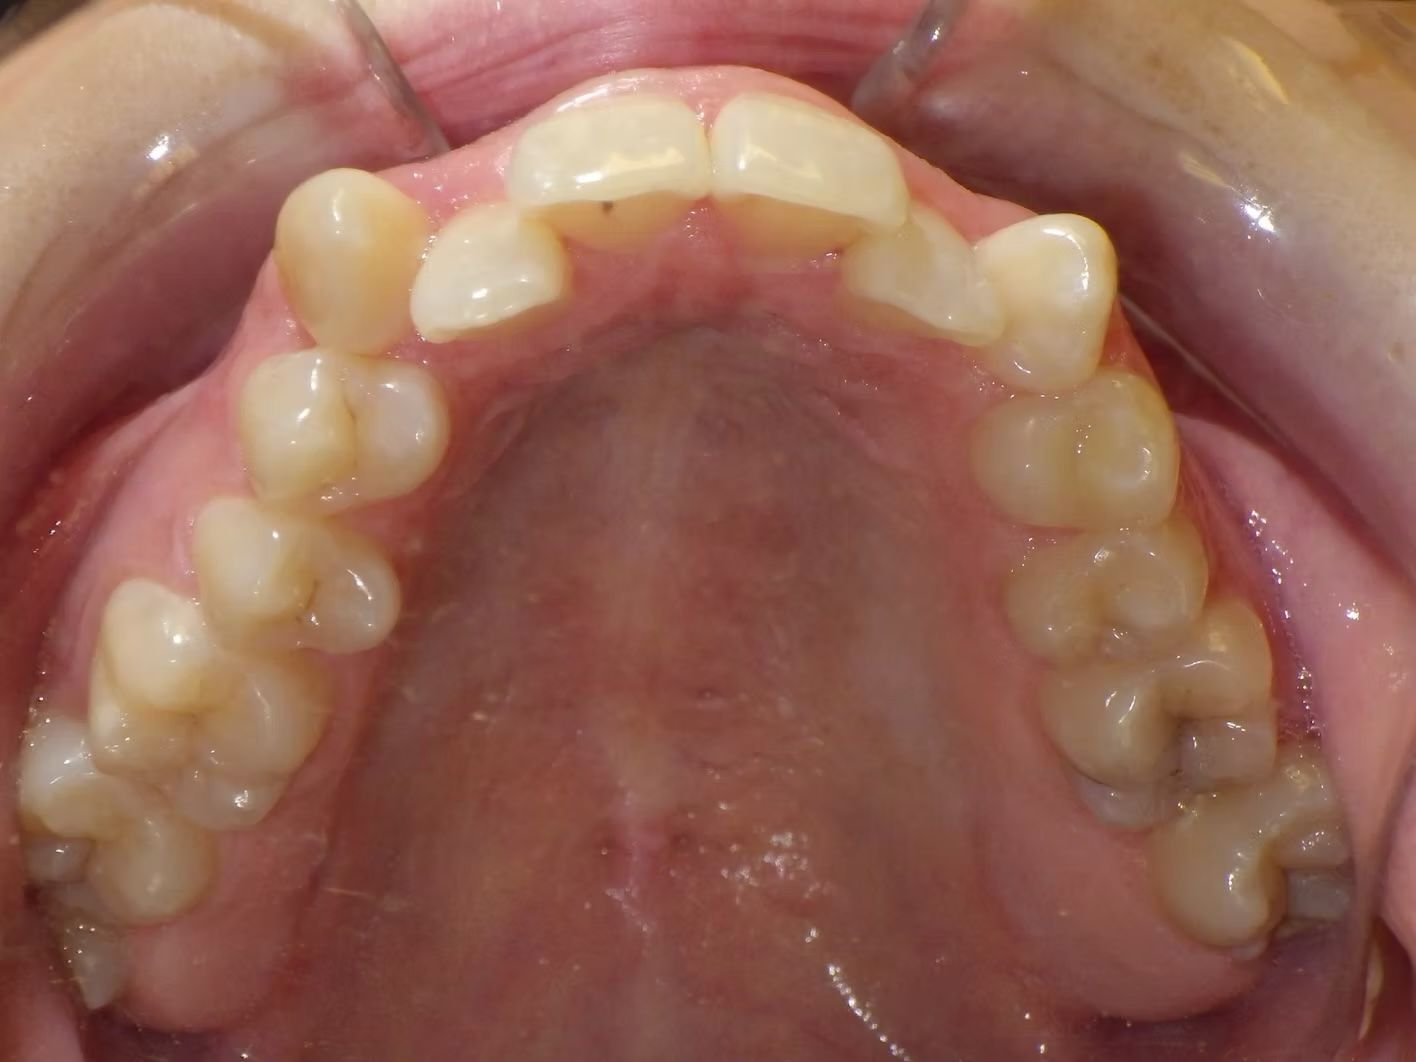

Fatima

Fatima didn't like her teeth. She was severely crowded in the top and lower dental arches. Her upper midline was off to the left. We extracted 4 teeth and lined up her teeth beautifully, corrected her bite and centered the upper and lower teeth with the face and each other.